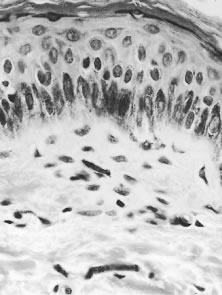

The earliest changes in the skin in onchocerciasis are mild and are often limited to a perivasculitis.14 In more heavily infected persons, microfilariae can be found, especially at the epidermal-dermal junction (Fig. 7). Live microfilariae are usually not surrounded by inflammatory cells.

Fig. 7. Microfilaria lying in the dermis. Although it has been cut into a number of sections, it is clearly recognizable, because the nuclei of the microfilaria are much smaller than those of the host cells. The absence of an inflammatory infiltrate around the microfilaria is characteristic (hematoxylin-eosin, ×700).